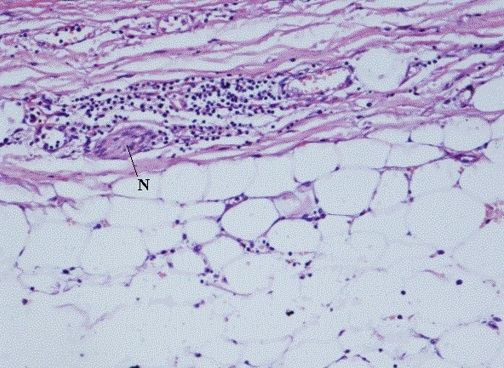

Autopsy findings. At autopsy, the heart (330 g of weight) showed a mild left ventricular hypertrophy and a marked but non occlusive coronarosclerosis. Histology showed myocardial signs of a recent acute ischemia and ventricular fibrillation and at the level epicardial layer of the heart a mild infiltration composed of mononuclear cells with a perivascular and perineural pattern of distribution. (Figure 1) These cells resulted positive to the immunostain for T lymphocyte marker CD 3. No expression for B lymphocyte and macrophage antigens (CD 20 and CD 68 respectively) were observed.

Figure 1. A perivascular lympho-mononuclear infiltration in the epicardial fatty tissue embracing a small nerve (N) (Ematoxylin-Eosin; 200 X original magnification)